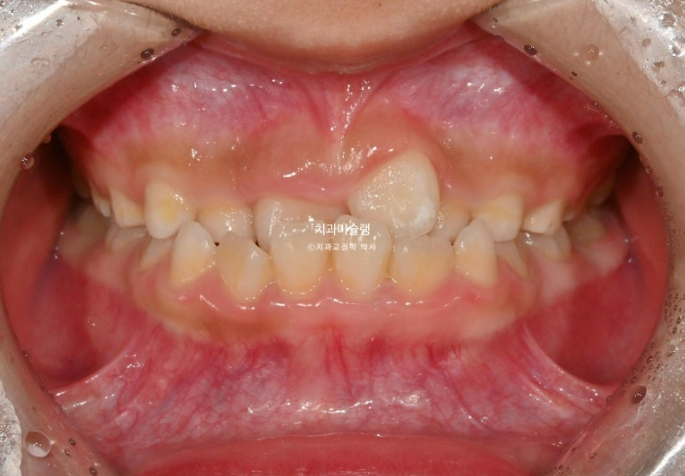

앞니가 거꾸로 물려서 온 7세 어린이 입니다.

윗니가 전체적으로 아랫니와 거꾸로 물리는 반대교합 입니다.

공간부족으로 앞니가 덧니처럼 나왔습니다.